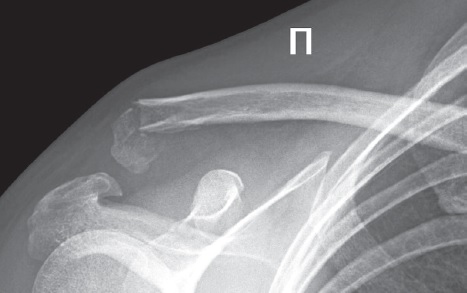

Пациентка 45 лет в августе 2022 г. получила травму области правого плеча в результате падения с лестницы с опорой на отведенную верхнюю конечность. При физикальном обследовании была выявлена деформация в области правого надплечья, резкая болезненность в проекции акромиально-ключичного сустава справа, положительный симптом «клавиши». Объем движений в плечевом суставе был резко ограничен на фоне выраженного болевого синдрома. На рентгенограмме области правого надплечья отмечались рентгенологические признаки закрытого перелома акромиального конца правой ключицы со смещением отломков в комбинации с закрытым переломом основания клювовидного отростка лопатки (рис. 1).

Рис. 1. Рентгенограмма правого акромиально-ключичного сустава в переднезадней проекции при поступлении: признаки закрытого перелома акромиального конца правой ключицы со смещением отломков в комбинации с закрытым переломом основания клювовидного отростка лопатки

Fig. 1. X-ray of the right acromioclavicular (AC) joint in AP view. Signs of closed fracture of the right distal clavicle with displacement of fragments combined with coracoid process fracture